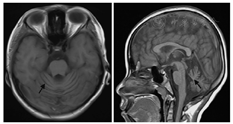

脑炎基因检测突变的分布可以识别出与疾病相关的突变,从而为临床提供更精准的诊断和个性化的治疗方案。 脑炎的基因突变分布具有一定的特征。研究表明,某些基因... 发生与基因突变有什么关系? 脑炎的发生与基因突变之间存在一定的关系。基因突变可能影响个体的免疫系统功能,使其对感染的抵抗力降低,从...